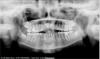

Jana Vladimirovna Опубликовано 9 сентября, 2009 Поделиться Опубликовано 9 сентября, 2009 Уважаемые ортодонты, у меня такая ситуация. Носила брекеты почти 3 года, после снятия было все хорошо. Врач не посчитал нужным ставить провочный ретейнер, а только изготовил пластинки. Спустя некоторое время пластинки стали малы, (была не в стране). Теперь спустя два года такое положение дел (зубов Есть ли какая нибудь альтернатива брекет -системам? Почему в большинстве клиниках мне отказываются ставить лингвальные брекеты (хотя такой вариант идеален по причине учебы, работы)? Буду признательна за любой совет! Заранее большое спасибо. Ссылка на комментарий